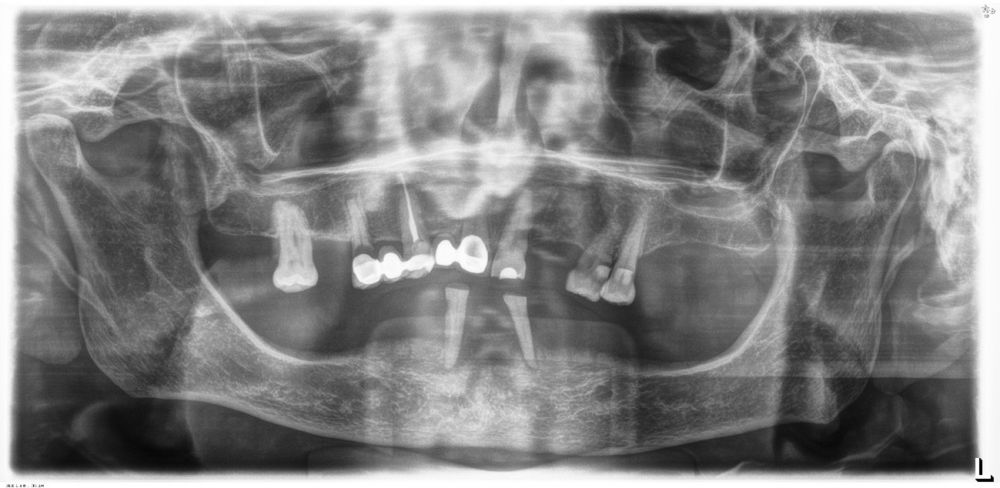

El análisis global de los 99 implantes reveló una pérdida ósea marginal media de 0,77 ± 0,26 mm en la superficie mesial y 0,79 ± 0,29 mm en la distal, valores que se mantuvieron dentro de los rangos considerados clínicamente aceptables para rehabilitaciones mandibulares. Cuando los implantes se categorizaron según su longitud, se observaron diferencias claras entre ambos grupos. Los implantes cortos (<10 mm) mostraron una pérdida ósea mesial media de 0,61 ± 0,23 mm y distal de 0,56 ± 0,22 mm, mientras que los implantes largos (≥10 mm) presentaron pérdidas significativamente mayores (mesial: 0,92 ± 0,19 mm; distal: 0,99 ± 0,17 mm). Dado que las pruebas de normalidad (Shapiro–Wilk) mostraron una distribución no normal en todos los grupos (p < 0,001), se aplicó la prueba no paramétrica de Mann–Whitney U. Los resultados confirmaron diferencias estadísticamente significativas tanto en la pérdida ósea mesial (U = 2068,5; p < 0,001) como en la distal (U = 2247,0; p < 0,005), indicando que los implantes cortos presentaron un comportamiento óseo más favorable que los implantes largos a lo largo del tiempo. Durante el tiempo de seguimiento que fue de media de 12,2 años (+/- 4,4; rango 6-23 años) no se objetivaron fracasos en ninguno de los implantes por lo que la supervivencia acumulada fue del 100%. El análisis del periodo de seguimiento mostró diferencias claras entre ambos grupos. Los implantes largos (≥10 mm) presentaron un tiempo medio de función de 14,1 ± 4,2 años (rango: 9–23 años), mientras que los implantes cortos (<10 mm) registraron un seguimiento significativamente menor, con una media de 9,8 ± 2,7 años (rango: 6–15 años). En las Figuras 3- 10 se muestran dos casos incluidos en el estudio, uno de cada situación descrita.

Un aspecto clave para interpretar estos resultados es el tiempo de seguimiento, ya que en nuestra cohorte los implantes largos presentaron significativamente más años en función intraoral. El análisis del periodo de seguimiento mostró diferencias claras entre ambos grupos. Los implantes largos (≥10 mm) presentaron un tiempo medio de función de 14,1 ± 4,2 años (rango: 9–23 años), mientras que los implantes cortos (<10 mm) registraron un seguimiento significativamente menor, con una media de 9,8 ± 2,7 años (rango: 6–15 años). La comparación mediante la prueba de Mann–Whitney U reveló diferencias estadísticamente significativas entre ambos grupos (p < 0,001). Este mayor tiempo en función de los implantes largos constituye un factor relevante a considerar en la interpretación de las diferencias observadas en la pérdida ósea marginal. La literatura demuestra que la pérdida ósea crestal es más pronunciada durante los primeros 12 meses y tiende a estabilizarse posteriormente, aunque existe un remodelado lento y continuo asociado al tiempo 36,48–50. Por tanto, es plausible que parte de la mayor pérdida ósea observada en los implantes largos esté relacionada con el mayor periodo de observación, aunque con los datos y el análisis realizado en el presente estudio, no podemos establecer esta correlación. Este factor debe considerarse al comparar ambos grupos y será analizado en estudios futuros con modelos de regresión ajustados por tiempo.

En relación con el voladizo, en nuestra cohorte únicamente las prótesis soportadas por implantes largos presentaban un mayor cantilever distal, mientras que las rehabilitaciones basadas en implantes cortos no lo requerían o tenían uno de longitud mínima. La literatura indica que la presencia de cantilever puede aumentar de forma significativa las tensiones sobre los implantes distales y favorecer el remodelado óseo marginal12,15,57–60. Este hecho podría contribuir a explicar las mayores pérdidas óseas del grupo de implantes largos, al margen del dato del tiempo de seguimiento anteriormente discutido y subraya la relevancia clínica de planificar rehabilitaciones sin voladizo siempre que la anatomía y los implantes cortos lo permitan. Finalmente, la estabilidad de las rehabilitaciones en ambos grupos confirma que el protocolo estandarizado aplicado en esta serie constituido por fresado biológico, carga progresiva y estructura híbrida atornillada sobre transepitelial, con implantes siempre paralelos, sin inclinaciones distales, proporciona un entorno favorable para la osteointegración y el mantenimiento periimplantario a largo plazo. Este enfoque coincide con las tendencias actuales hacia tratamientos mínimamente invasivos, pero biomecánicamente sólidos, reduciendo la necesidad de angulaciones extremas o regeneraciones complejas sin comprometer los resultados clínicos30,32,61,62.